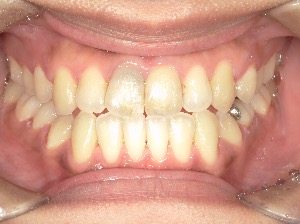

before

after

患者さんの年齢 20代 女性 症状 ガタガタを治したい 治療内容 マウスピース矯正治療 費用 90万(税抜) 治療期間・回数 治療期間2年、通院回数10回 メリット 笑顔が綺麗 デメリット・リスク 期間がかかることがある - マウスピース矯正